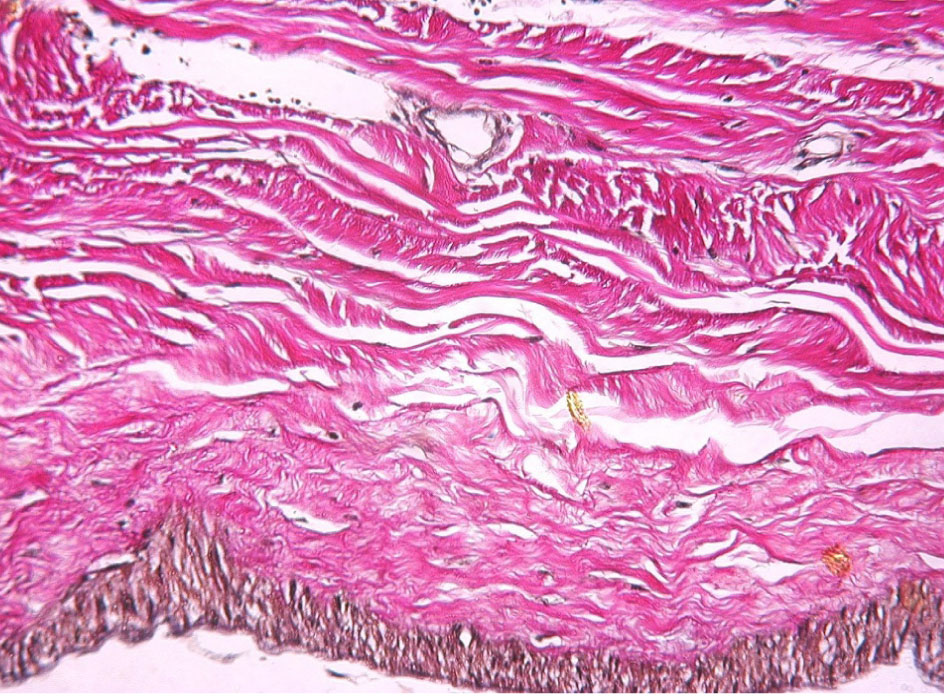

Морфологические характеристики ТМО. ТМО представляет собой белого цвета блестящую пластинку внутри и матово-серую снаружи. Она достаточно гладкая на ощупь и состоит из рыхло спаянных между собой двух листков, которые легко отделяются друг от друга – это надкостничная часть оболочки и менингеальная часть (рис. 1, 2) [11].

Рис. 1. ТМО мужчины 56 лет после извлечения головного мозга из полости черепа

По своей структуре ТМО представляет собой плотную неоформленную соединительную ткань, которая содержит сосуды микроциркуляторного русла. ТМО имеет четкую стратификацию своей гистоархитектоники и состоит из трех слоев – периостального, менингеального и погранично-клеточного (рис. 3) [7, 11].

Рис. 3. Фрагмент ТМО мужчины 30 лет. Окраска по Ван Гизону. Увеличение ×80

Каждый слой имеет определенную гистологическую специфику, которая делает его по своему уникальным. Самый наружный – это периостальный слой, прикрепленный к внутренней части черепа с богатым микроциркуляторным руслом и хорошо выраженной иннервацией. Он состоит из удлиненных фибробластов, формирующих скопления, с большими межклеточными пространствами. Средний слой – менингеальный, представлен большим количеством фибробластов и небольшим составом коллагена, в сравнении с периостальным слоем. Самым внутренним слоем ТМО является слой погранично-клеточный, который иногда величают внутренним слоем клеток, мезотелиальным слоем или нейротелием [7, 12, 13, 14]. Этот слой гораздо тоньше, нежели периостальный и менингеальный, граничит с паутинной оболочкой. Он представлен несколькими слоями клеток, имеющих некоторые особенности эпителия (десмосомы и тонофиламенты), и практически лишен соединительнотканных волокон во внеклеточном пространстве. Поскольку погранично-клеточный слой хрупкий и легко разрывается, он, вероятно, играет ключевую роль при возникновении субдуральной гематомы [13, 14].